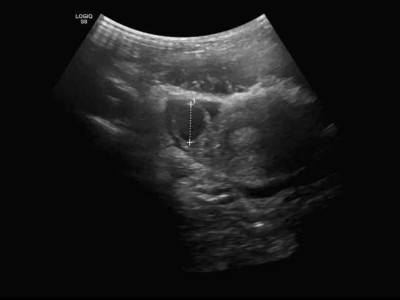

11-Jährige mit Bauchschmerzen: Was der Eileiter damit zu tun hat

Ein 11-jähriges Mädchen kommt mit rechtsseitigen Unterbauchschmerzen in die Notaufnahme. Labor-, Urin- und Ultraschalldiagnostik sind zunächst unauffällig. Erst in der zweiten Sonografie, nach einer erfolglosen Schmerztherapie, zeigt sich die seltene Ursache.

Bauchhoden/© Springer Medizin Verlag GmbH, Blutung im transversalen als auch im saggitalen Schnitt/© Institut für Diagnostische und Interventionelle Radiologie der Uniklinik Köln; mit freundlicher Genehmigung, Abdomensonographie: 14,7 mm große zystische Struktur im Bereich des rechten Ovars/© Isaev Y et al. / all rights reserved Springer Medizin Verlag GmbH, Röntgen einer Beckenfraktur und Abdomen-CT bei Jugendlichem/© Karvouniaris N. et al. / all rights reserved Springer Medizin Verlag GmbH, Drohende ösophago-arterielle Fistel nach Batterieingestion/© Lohmann J et al. doi.org/10.1007/s00101-024-01477-3 unter CC-BY 4.0, Kleinkind und Teddy mit Verband/© simoningate / Getty Images / iStock (Symbolbild mit Fotomodell), Akute Appendizitis/© Springer Medizin, Kind mit Gipsarm/© nycshooter / Getty Images / iStock (Symbolbild mit Fotomodell), Appendizitis /© Springer Medizin Verlag GmbH, Operationstechnik der Limberg-Plastik bei Sinus pilonidalis/© Jamal Driouch et al., Ärztin und Patientin im Gespräch/© andrei_r / Getty Images / iStock (Symbolbild mit Fotomodell), Bunte Plastikperlen/© Steven White / Getty Images / iStock, Ärztin betrachtet Röntgenbild/© dusanpetkovic1 / stock.adobe.com (Symbolbild mit Fotomodell), Search Icon, Knochensäge im Einsatz bei Knie-TEP/© Issara / stock.adobe.com (Symbolbild mit Fotomodellen), Hirntumoren sichtbar im MRT/© semnic / Getty Images / iStock (Symbolbild mit Fotomodell), Lungentrainer/© S@photo / stock.adobe.com (Symbolbild mit Fotomodell)